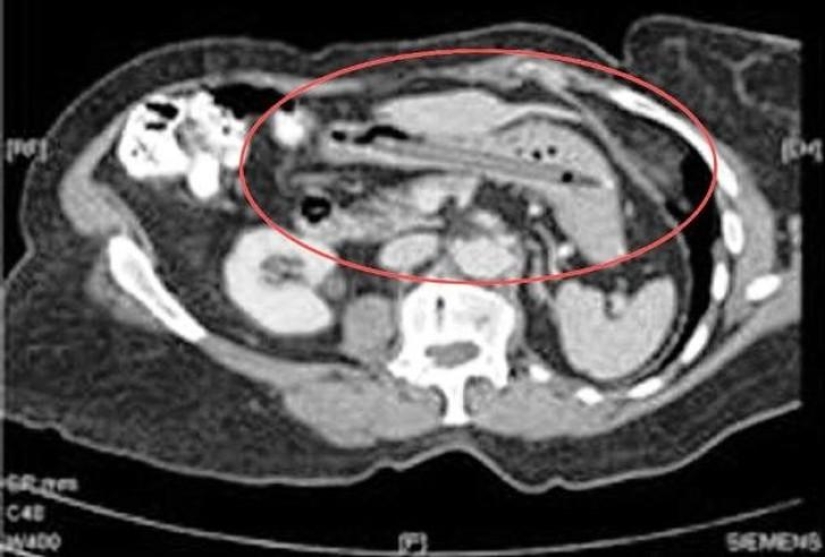

12. Cutlery.